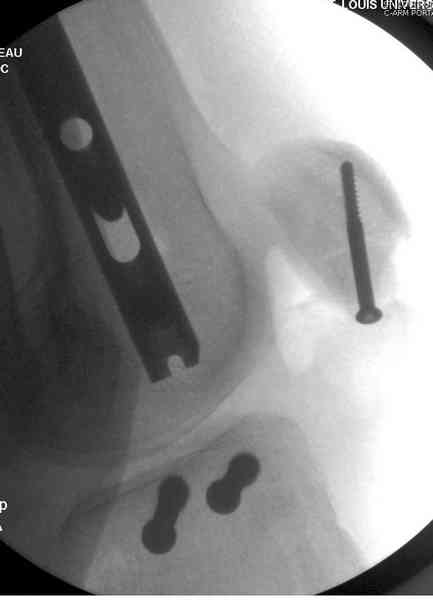

При высокоскоростных переломах редко можно встретить изолированную травму пилона, и в моей практике изолированные травмы большая редкость, поэтому, как дополнение к обсуждаемой теме, решил представить свежий, двухдневной давности случай.

Предыдущей сменой до 4:00 утра по поводу открытого перелома бедра, тибиал плато, пилон и надколенника сделана операция.

Пострадавшему 21 г., травма скоростная, после I&D с расширением раны, на бедре сделана операция ретроградным интрамедуллярным штифтом, остеосинтез с частичной резекцией надколенника и ушивание собственной связки.

В настоящее время больной в реанимации по поводу Черепно Мозговой Травмы и состояние улучшается. Запланировал ушивание раны в пятницу, если позволит состояние мягких тканей и при отсутстви отека возможно удастся просунуть перкутанномедиальную пластину.